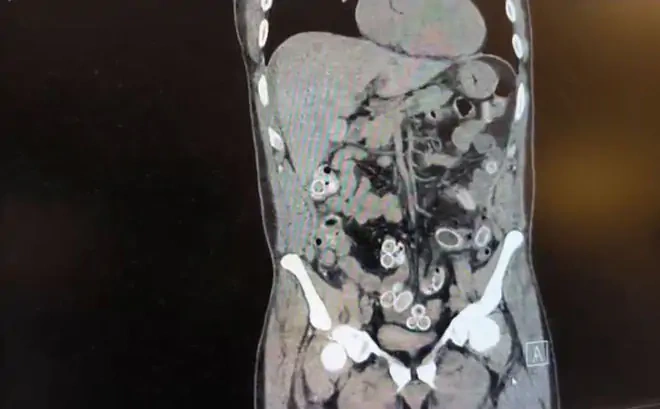

Tomografide yabancı madde tespit edildi

Muayene sırasında çekilen tomografide Cüneyt G.'nin mide ve bağırsaklarında yabancı cisimler görüldü.

Ameliyatta 49 kapsül esrar çıktı

Doktorların değerlendirmesiyle ameliyata alınan şüphelinin bağırsaklarından 49 adet esrar macunu kapsülü çıkarıldı.

Toplam ağırlığı 259.7 gram olan uyuşturucu maddeye el konuldu.